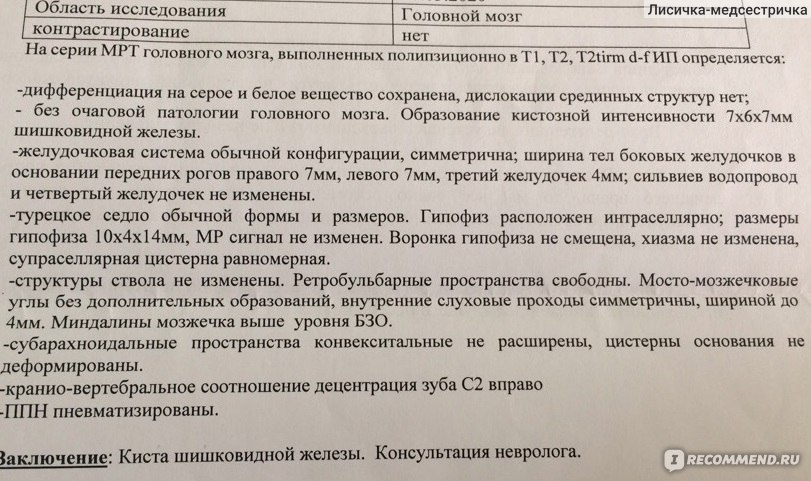

МРТ головного мозга: Расшифровка снимков и Интерпретация

Раздел: Визуальные уроки